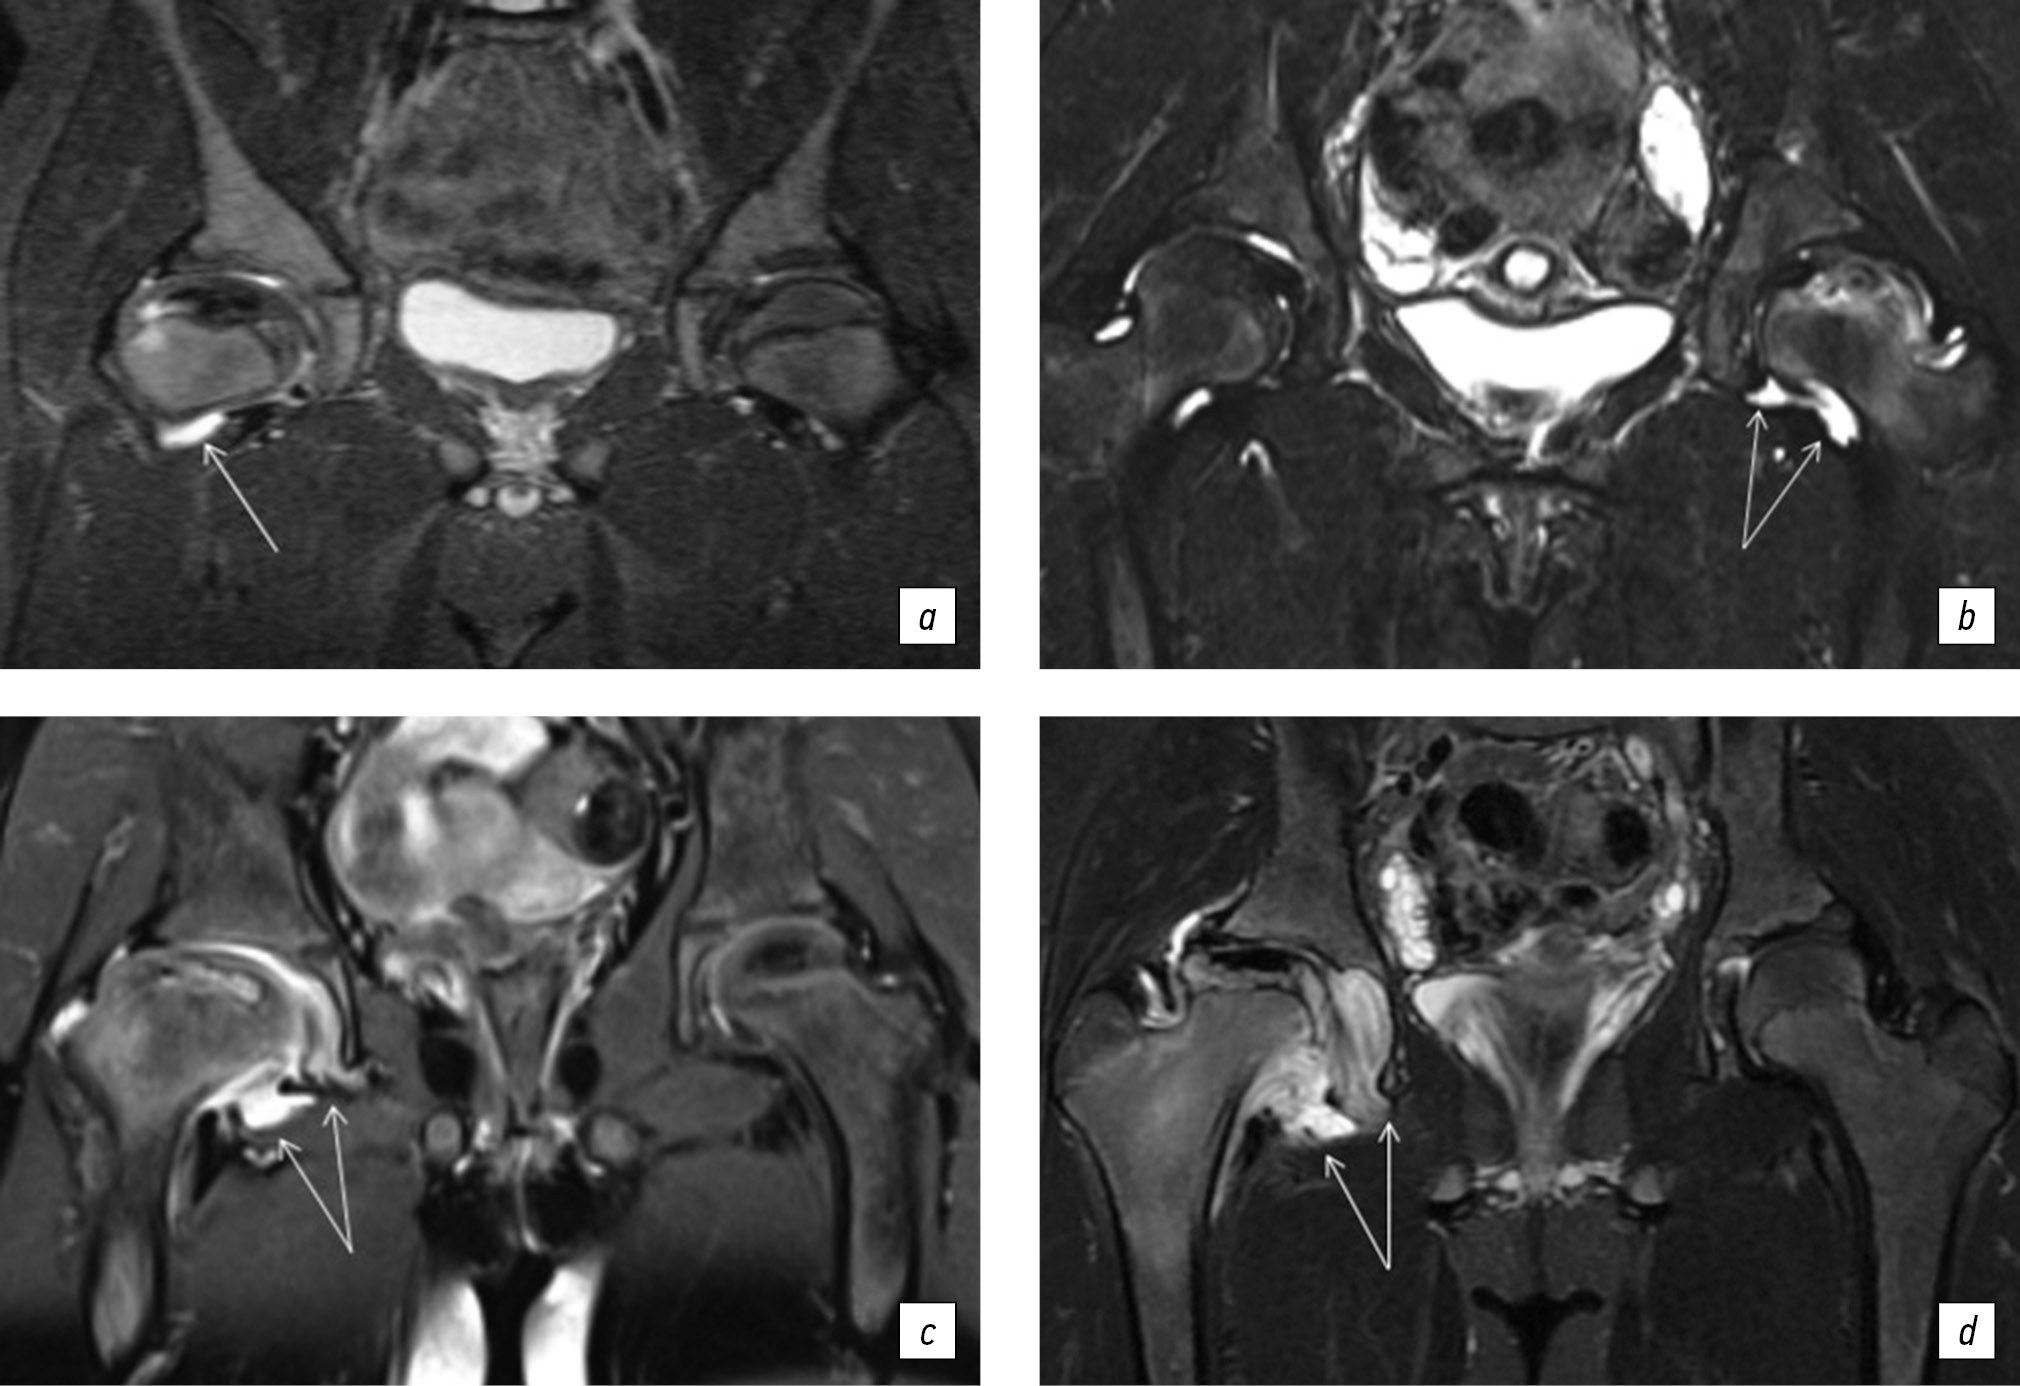

Для оценки воспаления тазобедренного сустава по шкале SCORING OF HIP MRI FOR JIA определяли степень утолщения синовиальной оболочки и наличие выпота. Измерения проводили на T2 STIR в коронарной плоскости два рентгенолога. При подсчете МР-признаков воспаления использовали градацию от 0 до 3, где 0 — отсутствие выпота и утолщения синовиальной оболочки; 1 — минимальное скопление выпота в капсуле сустава; 2 — умеренное скопление синовиальной жидкости с растяжением капсулы сустава и реакцией синовиальной оболочки; 3 — значительное скопление синовиальной жидкости с растяжением капсулы сустава и пролиферацией синовиальной оболочки (рис. 2).

Рис. 2. Магнитно-резонансная томограмма: признаки различной степени выраженности синовита тазобедренного сустава у детей с болезнью Легга – Кальве – Пертеса. В режимах STIR представлены: минимальное скопление выпота в капсуле сустава (а); умеренное скопление синовиальной жидкости с растяжением капсулы сустава и реакцией синовиальной оболочки (б, в); значительное скопление синовиальной жидкости с растяжением капсулы сустава и пролиферацией синовиальной оболочки (г)